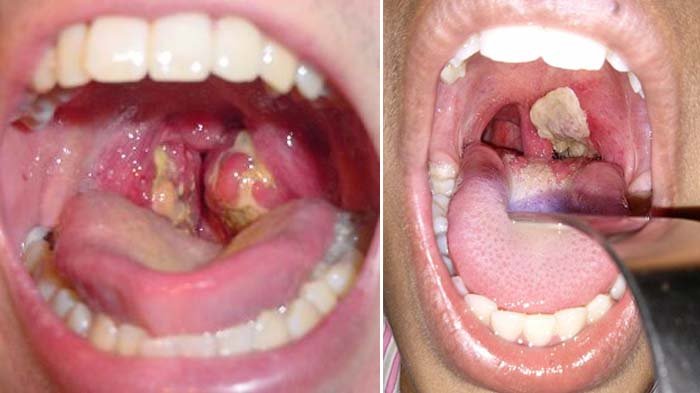

Difteri disebabkan oleh bakteri Corynebacterium diphtheriae.